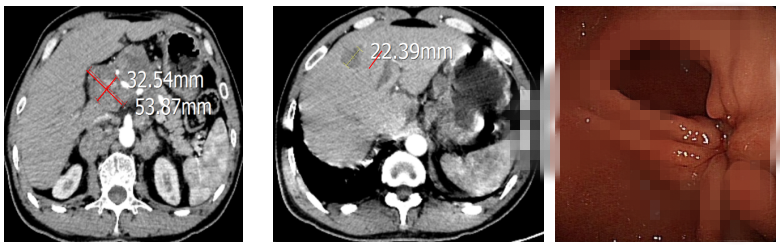

王慧娟主任医师组织科室讨论详细分析了文某的病情,与患者及家属充分沟通后,于2021年10月—2022年2月行一线6周期姑息性化疗。每两周期复查提示病情评估为稳定(病灶缩小但达不到部分缓解),患者症状较前缓解。2022年3月患者出现左侧颈部淋巴结增大(4cm),评估病情后提示病情进展,行颈部淋巴结穿刺活检,病理结果及PD-L1检测示:(淋巴结)转移性腺癌,PDL1(sp263)TPS<1%,CPS<1%,Her-2阴性。再次与患者及家属沟通后,调整为免疫检查点抑制剂联合二线全身静脉化疗6周期。1周期治疗后患者颈部淋巴结明显减小。2周期后影响评估:部分缓解(PR)。此后患者每3周予以免疫检查点抑制剂维持治疗,直至目前,患者已免疫治疗1年,2023年4月复查CT、胃镜提示颈部淋巴结、胃窦溃疡、肝转移病灶几近消失,病情依然稳定。目前患者已安全度过18月余,我院化疗科会继续随访此患者,同时希望更多朋友保持健康的饮食规律,定期体检,早发现、早诊断、早治疗。

一线6周期化疗后腹部CT及胃镜